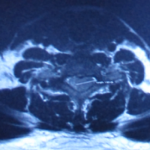

割除椎管腫瘤